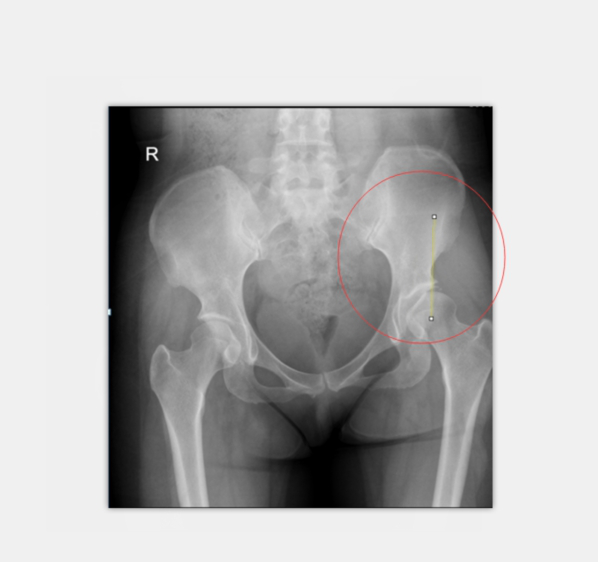

术前X光:患者左髋臼CE角约0度

诊断考虑:先天性髋臼关节发育不良

术后X光:CE角约26度,髋臼尺度正常